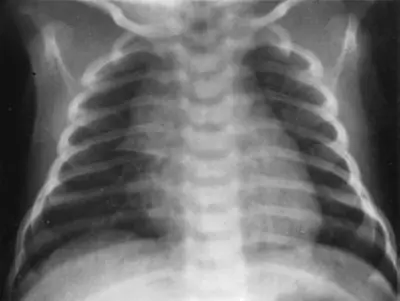

本題附圖之嬰兒胸部 X光可看到什麼?

嬰兒胸部 X 光的正常胸腺(thymus)影像特徵辨識。本題考查嬰兒期常見的胸腺顯影(thymic shadow)在胸部 X 光上的正確判讀,避免誤判為心臟擴大或肺部病變。

此嬰兒胸部 X 光可見:

- 上縱膈腔(superior mediastinum)增寬:整個上縱膈腔有明顯的軟組織密度陰影向兩側延伸

- 右側特徵性帆狀突出(sail sign):右上縱膈可見一個三角形、密度均勻的陰影,其外側緣凸出且下方邊緣筆直,如帆船的帆,此即為典型的「胸腺帆狀徵(thymic sail sign)」

- 胸腺波浪徵(thymic wave sign):胸腺外緣可見因肋骨壓迫而形成的波浪狀輪廓,這是正常柔軟胸腺組織的特徵,可與縱膈腫瘤鑑別

- 心臟輪廓:心臟本身大小尚屬正常範圍,心臟下緣清楚可辨

- 肺野:兩側肺野透明度正常,無明顯滲潤或浸潤影

結論:此影像為嬰兒期正常胸腺顯影,呈現典型的 sail sign,屬正常生理現象,非病理狀態。

(A) 胸腺(thymus) ✅ 正確答案 嬰兒(尤其是 2 歲以下)的胸腺相對於身體比例較大,在胸部 X 光上可呈現:

- 帆狀徵(sail sign):右側胸腺呈三角形帆狀突出